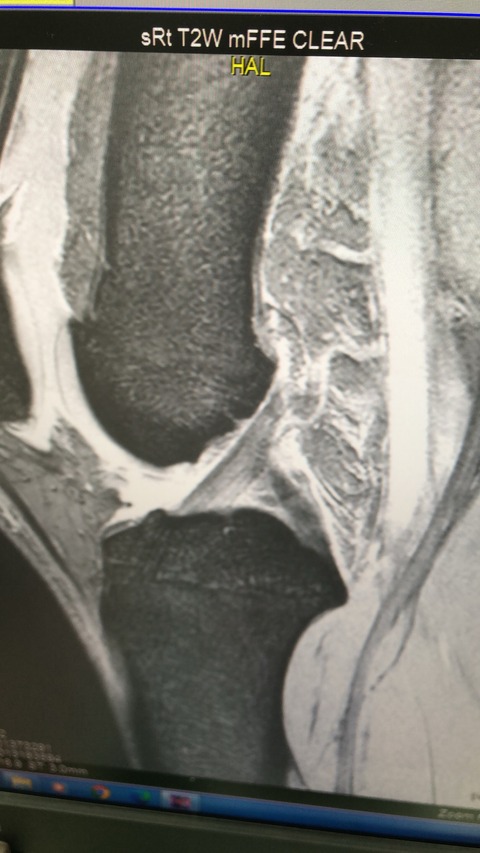

デッドボール受けた瞬間に膝を強く捻り受傷

MRIで前十字靭帯の部分断裂、半月板の損傷が

ありますが、3週間で、現在のところを幸い、

全く痛みなく、普通にジョギング等

できるなりました

トレーナー、監督、本人と相談の上、

今シーズンは、復帰させます